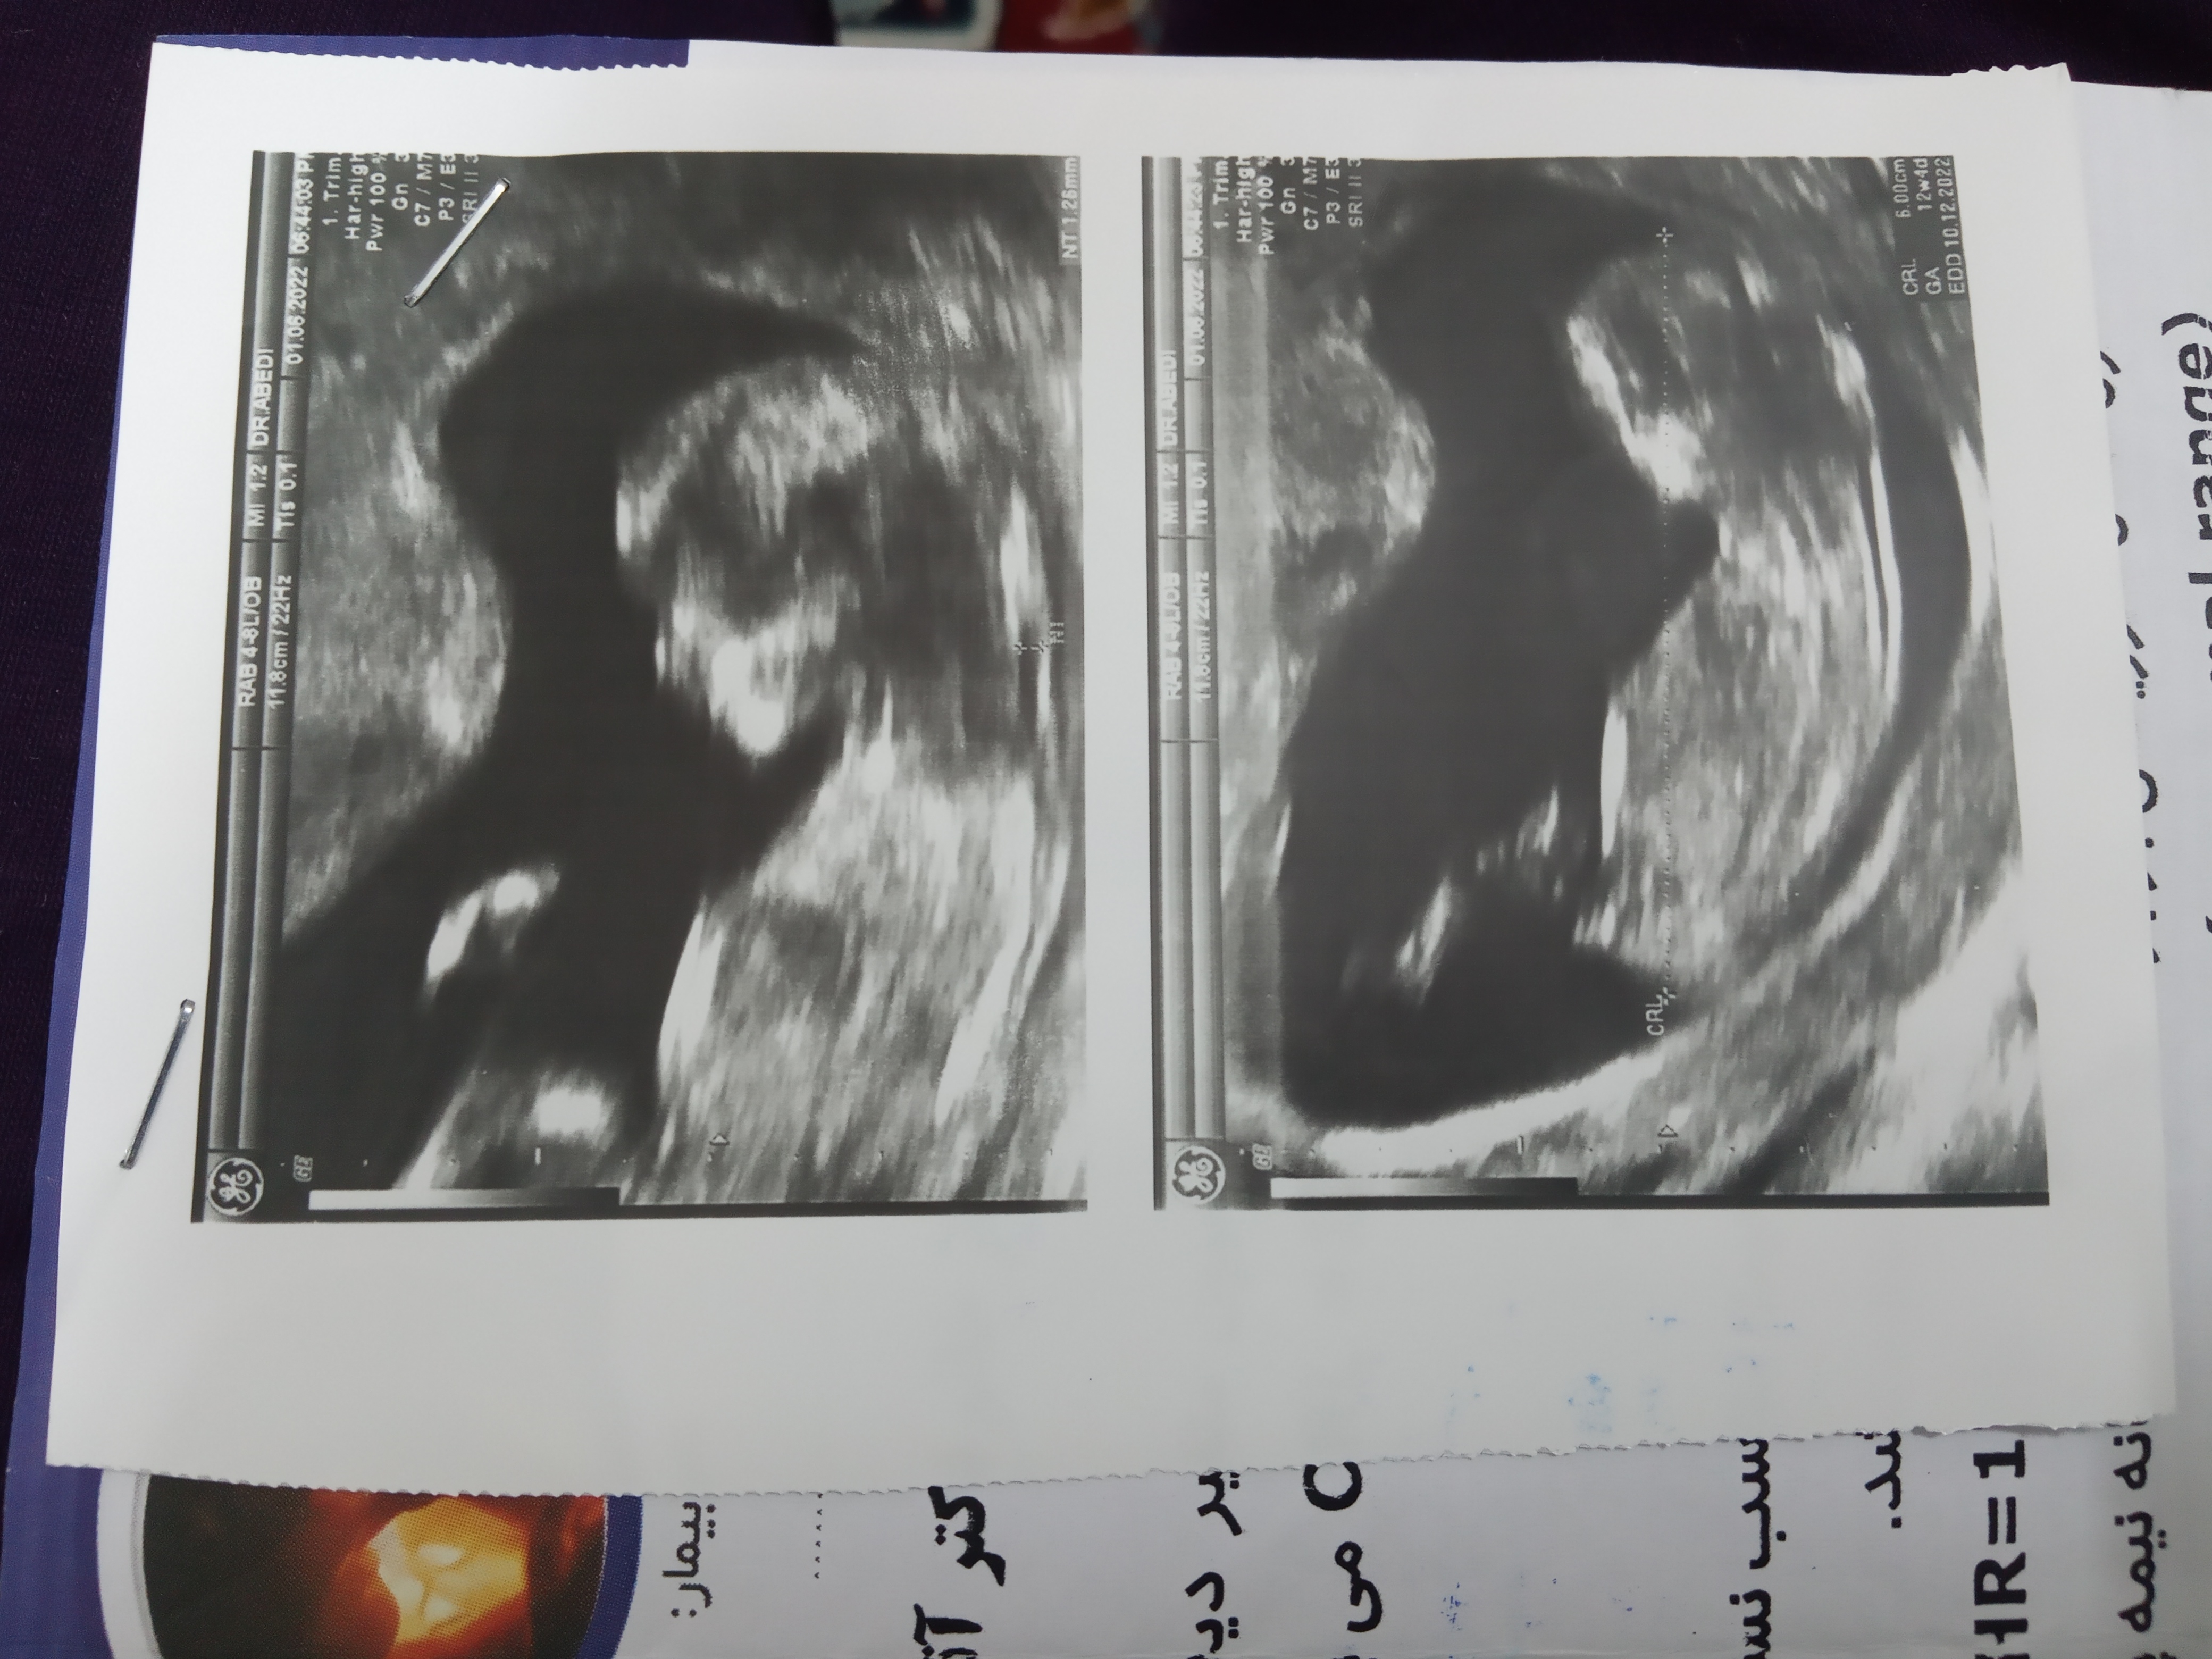

دکترا سنوگرافیم نمیگن صدرصد

عروس عمه م دکتر گف بچه پاشو جمع کرده ولی به نظر به احتمال زیاد دختره

سونوگراف فقط خودت..بقیه الکی وقتشونو هدر دادن